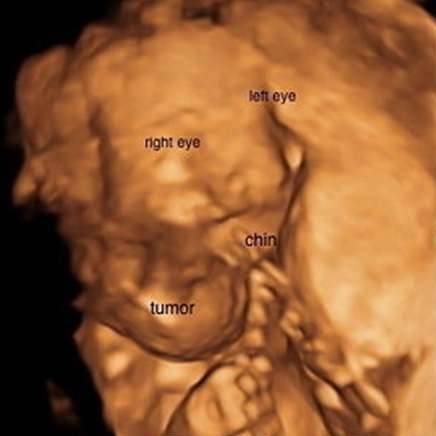

▼超音波显示宝宝的脖子上有个异样突起,医生认为这是一种谜样的「畸胎瘤」(teratoma),事情的真相只能透过核磁共振成像来进一步推测。

▼三週后,琳赛进行了核磁共振成像,他们最害怕的事情发生了:欧玛拉肿瘤的体积扩大了三倍,而且还蔓延到她的头部、胸部、肺部以及眼睛,这已经不是手术可以救援的…

▼然而,等到医生帮她照核磁共振时,却发现欧玛拉的状况显然比那位小女孩糟多了。欧玛拉得的是一种侵略性的淋巴瘤,它们已经在她脑内滋长,甚至膨胀成了三倍,这只能导向一个结局:死亡。

▼生出欧玛拉后,他们可以清楚看到她脖子上肿瘤的肿胀程度,「我们都被吓到了。」琳赛指出,欧玛拉的肿瘤其实在出生后已经排空不少,所以这些照片还是在她肿瘤比较小的时候拍摄的。